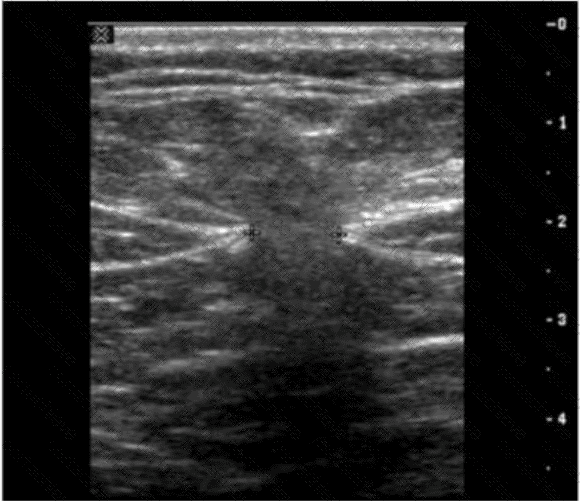

QUESTION DESCRIPTION:

Which vascular condition is most likely associated with the sonographic findings demonstrated in this image?

Correct Answer & Rationale:

Answer: C

Explanation:

The ultrasound image demonstrates a tubular, anechoic structure coursing anterior to the left portal vein and heading toward the anterior abdominal wall. This is consistent with a recanalized umbilical vein, which is an important collateral pathway that reopens in cases of portal hypertension.

Normally, the umbilical vein becomes obliterated after birth and forms the ligamentum teres. However, in the setting of significant portal hypertension, the umbilical vein may recanalize and serve as a collateral route to decompress the portal system.

Sonographic features of a recanalized umbilical vein:

Anechoic, tubular structure in the ligamentum teres fissure

Seen anterior to the left portal vein

Color Doppler confirms hepatofugal venous flow

Associated with signs of portal hypertension (e.g., splenomegaly, varices)

Differentiation from other options:

A. Budd-Chiari syndrome: Involves hepatic vein outflow obstruction; ultrasound shows absent or narrowed hepatic veins and may have caudate lobe hypertrophy.

B. Splenic artery aneurysm: Typically visualized near the splenic hilum as a pulsatile cystic mass; Doppler shows arterial flow.

D. Median arcuate ligament syndrome: Involves compression of the celiac axis; best assessed with Doppler showing elevated velocities on expiration.